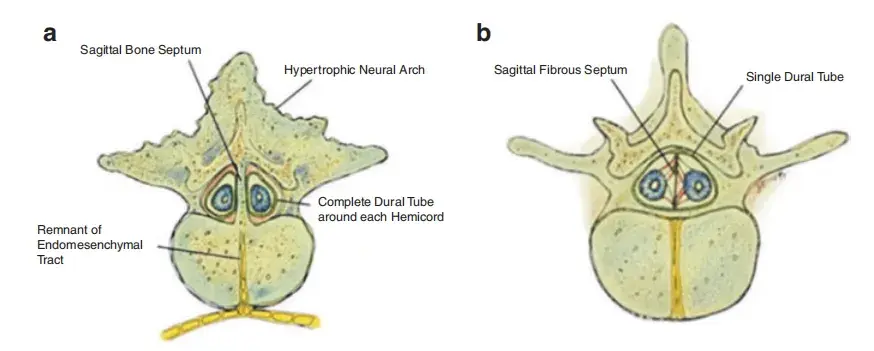

花季少女小雨(化名)从小患上一种怪病,后腰的位置上长了些毛发,而且越长越多。更令人担心的是,小雨突然出现腰疼和腿部不适的症状。最终诊断包含脊髓的纵裂、脊髓栓系综合征、椎板...

脊柱和脊髓闭合不全(DMSSC)代表了一系列先天性畸形,推测其起源于早期胚胎发生的缺陷。这些疾病的临床后果影响全世界儿童的发育。尽管相对常见(估计发病率为1-3/1000活产儿),但其病...